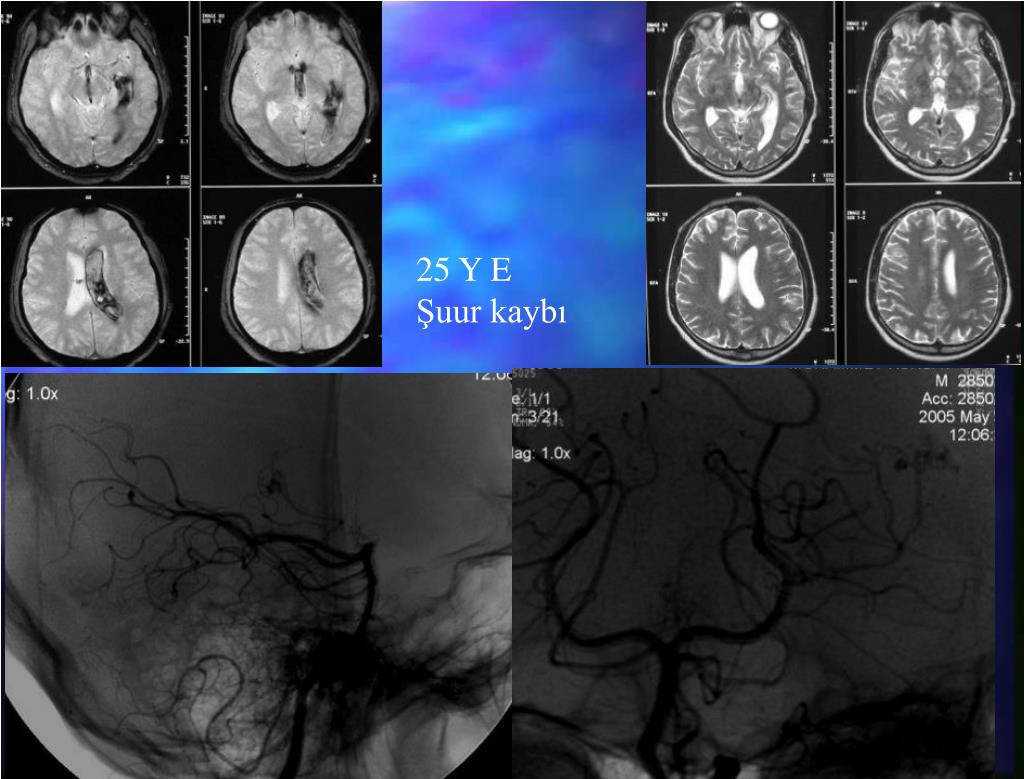

24. 25 Y E Şuur kaybı